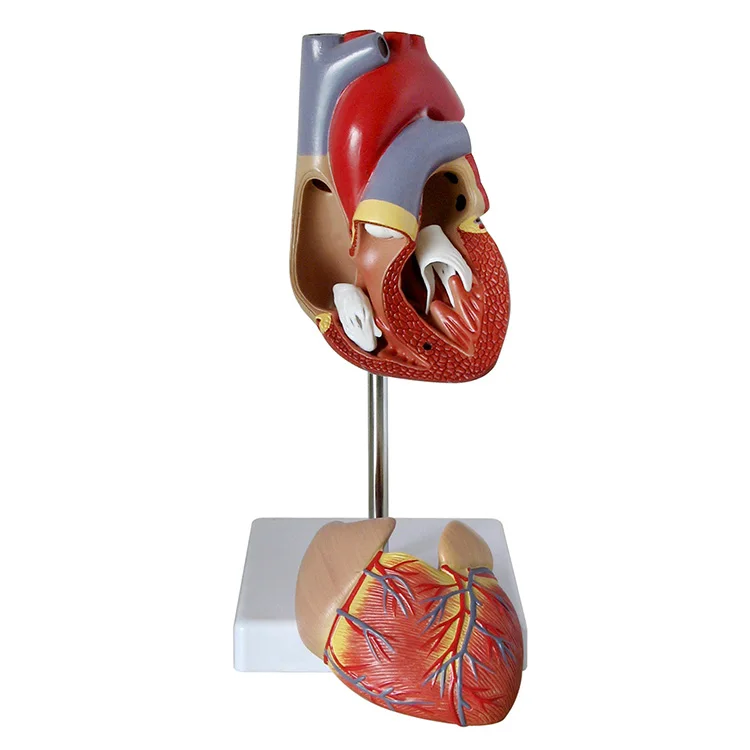

Valentine’s Day ช็อกโกแลตหัวใจ 12 ชิ้น – ของขวัญรังนกแท้ คอซซี่ โมเดลหัวใจมนุษย์ (Human Heart) | Shopee Thailand

โมเดลหัวใจมนุษย์ (Human Heart) | Shopee Thailand หัวใจมนุษย์ ภาพสต็อก – ดาวน์โหลดรูปภาพตอนนี้ – หัวใจ – อวัยวะภายใน …

ขยายกายวิภาคหัวใจมนุษย์รุ่น 3 ชิ้นส่วน – Buy กายวิภาคหัวใจ,หัวใจ … หัวใจมนุษย์ การออกแบบรายละเอียด ภาพประกอบสต็อก – ดาวน์โหลดรูปภาพตอนนี้ …

ชีวิตพลาสติกกายวิภาคหัวใจมนุษย์รุ่น2ชิ้นส่วน – Buy การสอนรุ่น,Anatomy … ช็อคโกแลตรูปหัวใจ [ภาพวาดฟรี] | OkusanPix

หัวใจวิทยาศาสตร์เรื่องกายวิภาคศาสตร์ทางการแพทย์หัวใจมนุษย์รุ่นขาย – Buy … รูปเวกเตอร์ฟรีหัวใจการ์ตูนปุ่ม PNG , หัวใจมนุษย์, หัวใจ, เซลล์ภาพ PNG …

รักสุดใจ! ช่อช็อกโกแลตให้เธอ รวมไอเดียช่อช็อกโกแลตสื่อรัก มอบให้แฟน แบบจำลองหัวใจมนุษย์ขนาดชีวิตที่มีสีพื้นโปร่งใสโรคหัวใจทางการแพทย์แบบ …

แบบจำลองหัวใจมนุษย์ขนาดชีวิตที่มีสีพื้นโปร่งใสโรคหัวใจทางการแพทย์แบบ … Chocolate Heart, Hand-drawn sketch Chocolate s, brown, food png | PNGEgg

Chocolate Heart, Hand-drawn sketch Chocolate s, brown, food png | PNGEgg แบบจำลองหัวใจมนุษย์ขนาดชีวิตที่มีสีพื้นโปร่งใสโรคหัวใจทางการแพทย์แบบ …

แบบจำลองหัวใจมนุษย์ขนาดชีวิตที่มีสีพื้นโปร่งใสโรคหัวใจทางการแพทย์แบบ … ช็อกโกแลต รูปฟุตบอล เหรียญทอง หัวใจ บรรจุ 60 ชิ้น | Shopee Thailand

In-306 3d กายวิภาคศาสตร์หัวใจมนุษย์รูปแบบทางการแพทย์พลาสติกกายวิภาค … หัวใจมนุษย์ ภาพสต็อก – ดาวน์โหลดรูปภาพตอนนี้ – หัวใจ – อวัยวะภายใน, การ …

หัวใจวิทยาศาสตร์เรื่องกายวิภาคศาสตร์ทางการแพทย์หัวใจมนุษย์รุ่นขาย – Buy … หัวใจวิทยาศาสตร์เรื่องกายวิภาคศาสตร์ทางการแพทย์หัวใจมนุษย์รุ่นขาย – Buy …

หัวใจวิทยาศาสตร์เรื่องกายวิภาคศาสตร์ทางการแพทย์หัวใจมนุษย์รุ่นขาย – Buy … Anatomy หัวใจมนุษย์รุ่นพลาสติกทางการแพทย์กายวิภาคหัวใจจัมโบ้รุ่นอวัยวะ …

Anatomy หัวใจมนุษย์รุ่นพลาสติกทางการแพทย์กายวิภาคหัวใจจัมโบ้รุ่นอวัยวะ … รูปช็อกโกแลตหัวใจพร้อมน้ำเชื่อม PNG , วาเลนไทน์วัน, หัวใจ, วันแห่งความ …

3d Anatomy หัวใจมนุษย์รุ่นพลาสติกทางการแพทย์กายวิภาคหัวใจจัมโบ้รุ่น … หัวใจวิทยาศาสตร์เรื่องกายวิภาคศาสตร์ทางการแพทย์หัวใจมนุษย์รุ่นขาย – Buy …

หัวใจวิทยาศาสตร์เรื่องกายวิภาคศาสตร์ทางการแพทย์หัวใจมนุษย์รุ่นขาย – Buy … ส่งไว🚀24ชม. เจบีช็อกโกแลต รูปฟุตบอล เหรียญทอง เหรียญเงิน ทองแท่ง หัวใจ …

ส่งไว🚀24ชม. เจบีช็อกโกแลต รูปฟุตบอล เหรียญทอง เหรียญเงิน ทองแท่ง หัวใจ … Anatomy หัวใจมนุษย์รุ่นพลาสติกทางการแพทย์กายวิภาคหัวใจจัมโบ้รุ่นอวัยวะ …

Anatomy หัวใจมนุษย์รุ่นพลาสติกทางการแพทย์กายวิภาคหัวใจจัมโบ้รุ่นอวัยวะ … ภาพประกอบแบนเวกเตอร์หัวใจมนุษย์ขนาดใหญ่บนพื้นหลังสีขาว ภาพประกอบสต็อก …

หัวใจมนุษย์กายวิภาครุ่นวิทยาศาสตร์การแพทย์รูปแบบการสอน ห้องหัวใจมนุษย์: คำอธิบายโครงสร้างหน้าที่และประเภท

หุ่นจำลองหัวใจมนุษย์ 3d มนุษย์กายวิภาครุ่นหัวใจมนุษย์สำหรับซัพพลายเออร์แบบครบวงจรวิทยาศาสตร์ …

3d มนุษย์กายวิภาครุ่นหัวใจมนุษย์สำหรับซัพพลายเออร์แบบครบวงจรวิทยาศาสตร์ … 3d Anatomy หัวใจมนุษย์รุ่นพลาสติกทางการแพทย์กายวิภาคหัวใจจัมโบ้รุ่น …

3d Anatomy หัวใจมนุษย์รุ่นพลาสติกทางการแพทย์กายวิภาคหัวใจจัมโบ้รุ่น … อวัยวะหัวใจของมนุษย์ | องค์ประกอบกราฟฟิก แบบ PSD ดาวน์โหลดฟรี – Pikbest

หัวใจมนุษย์กายวิภาครุ่นวิทยาศาสตร์การแพทย์รูปแบบการสอน 15 Porch ช็อกโกแลต Fudge แม่พิมพ์ซิลิโคนหัวใจรูปเค้กช็อกโกแลตตกแต่ง DIY …

อุปกรณ์การศึกษากายวิภาคศาสตร์รุ่นหัวใจมนุษย์รุ่นสำหรับโรงเรียนขนาดชีวิต … วิธีทำ “นามะช็อกโกแลต” ของฝากยอดฮิตจากญี่ปุ่น อร่อยหรูดูแพง แต่ทำง่าย …

In-306 3d กายวิภาคศาสตร์หัวใจมนุษย์รูปแบบทางการแพทย์พลาสติกกายวิภาค … บอลลูนหัวใจมนุษย์ Angioplasty เวกเตอร์ ภาพประกอบ ภาพประกอบสต็อก – ดาวน์ …

โรงงานโดยตรงขาย Anatomy หัวใจมนุษย์การฝึกอบรมชุดอวัยวะภายในรุ่น – Buy …